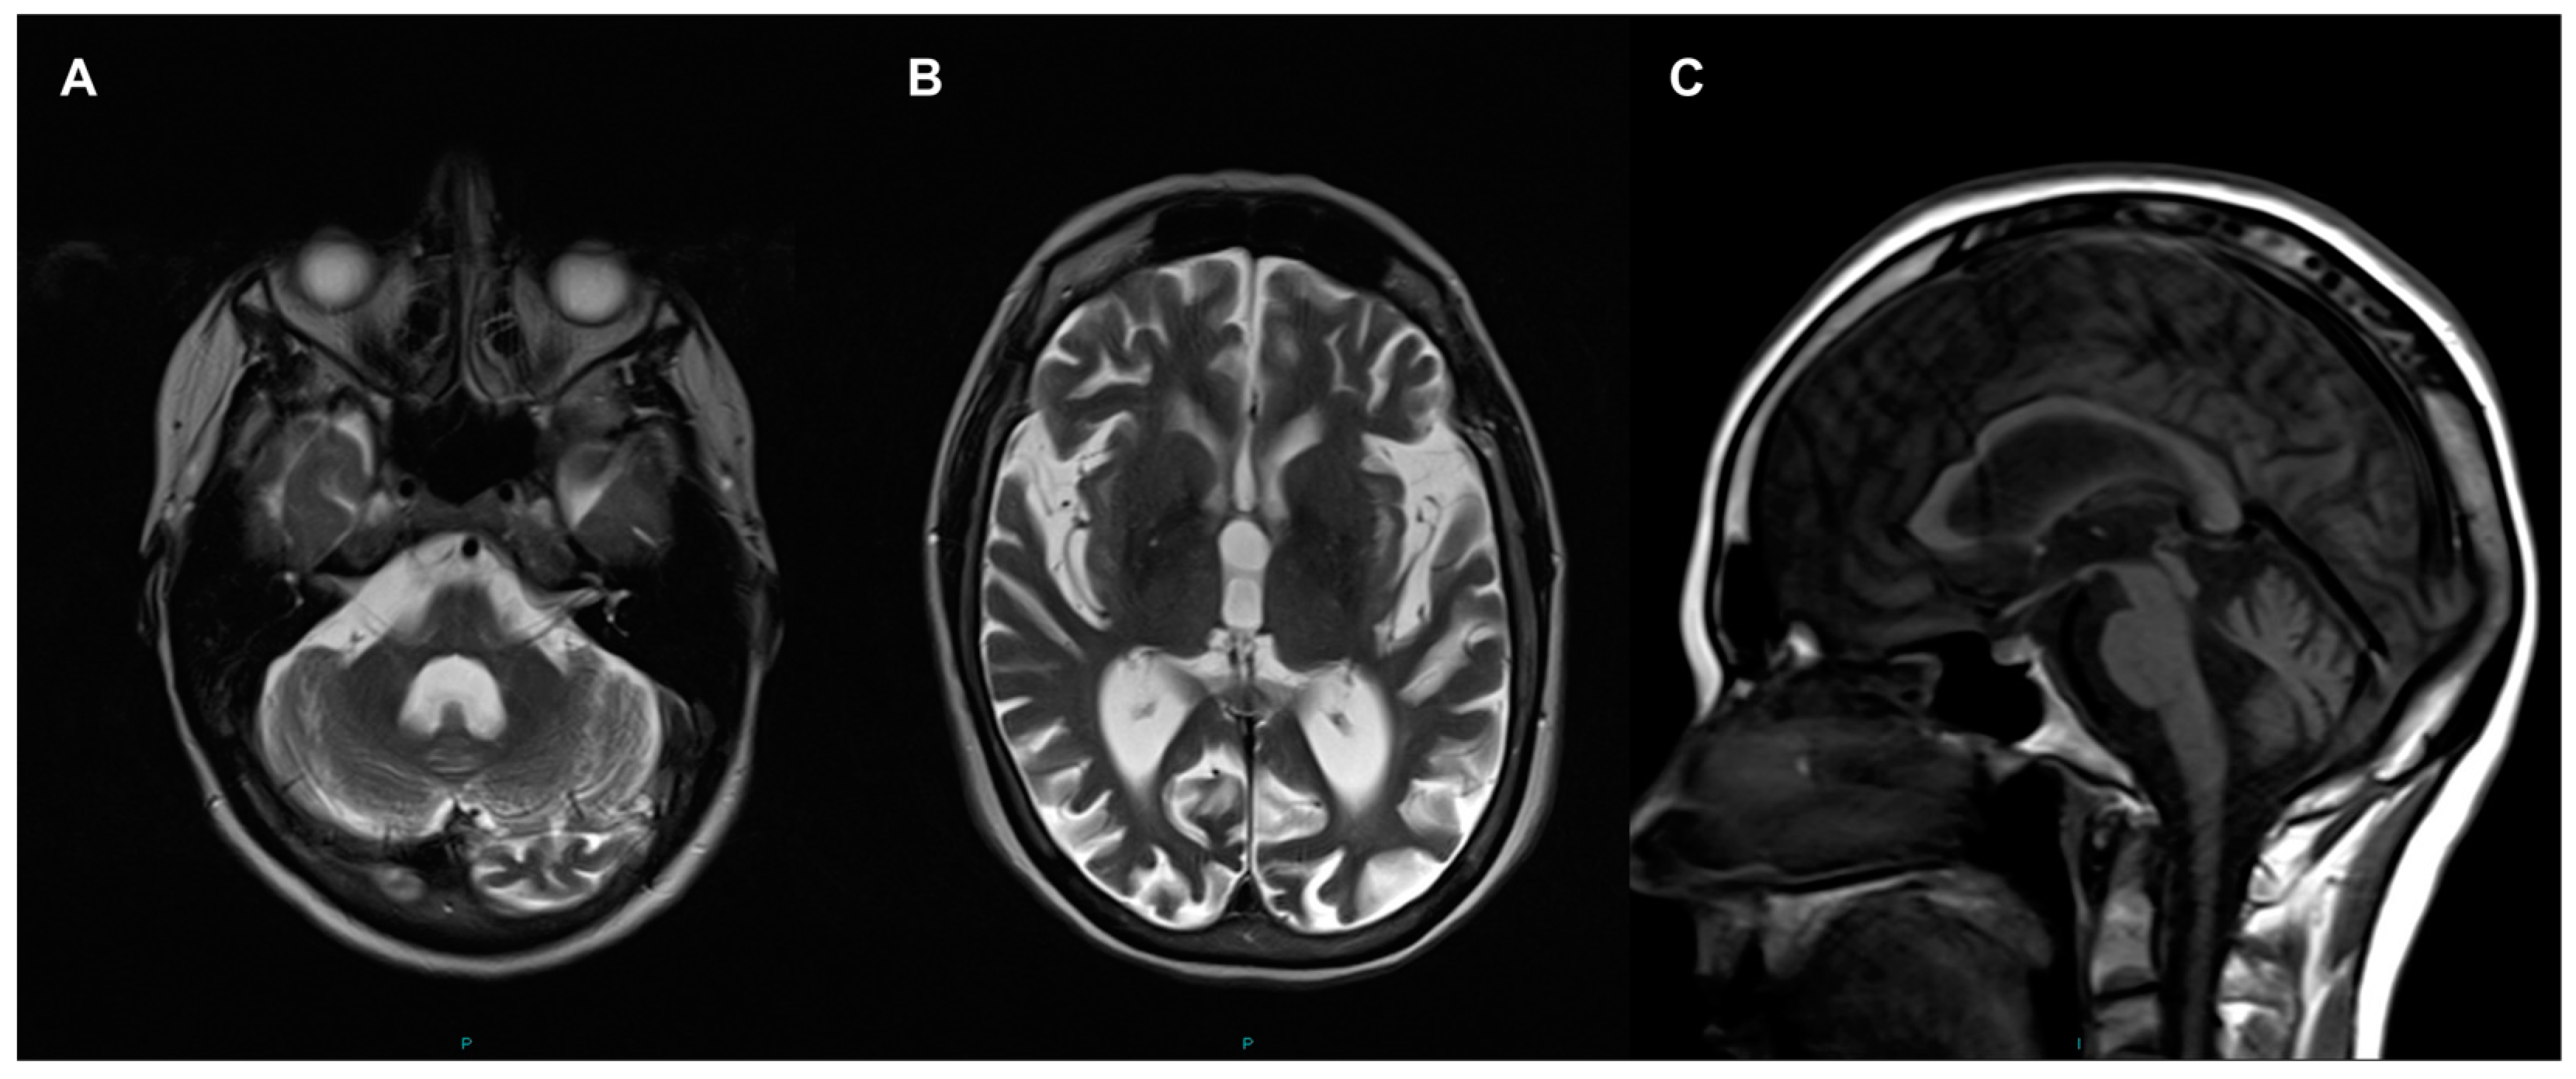

2.1. Case Report